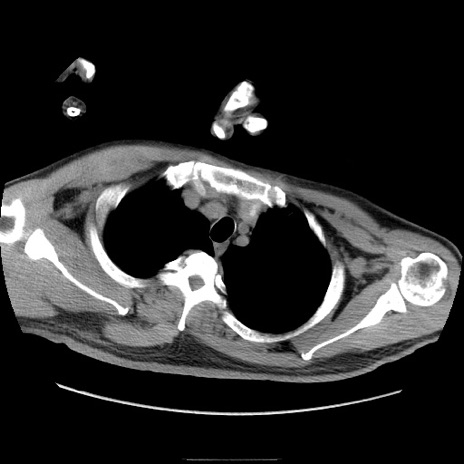

冠状断像

【症例】50歳代男性

【主訴】腹痛

【現病歴】AVMからの被殻出血のため回復期リハ病棟入院中。 本日午後3時頃急に下腹部痛が出現した。

【既往歴】AVM、被殻出血、虫垂炎、高血圧

【身体所見】意識晴明、左半身不全麻痺、会話の理解は良好、36.5°C、腹部:膨隆、全体に板状硬、下腹部正中に圧痛点あり、反跳痛-、筋性防御不明、右下腹部にope scar

【データ】WBC 9400、CRP 0.06